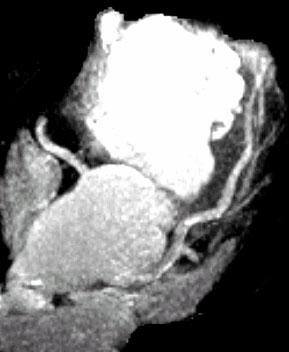

Появились методики виртуальной КТ-ангиоскопии, колоноскопии, бронхоскопии, пельвио- уретероскопии, цистоскопии, ларингоскопии и подобные им методы (Рис.3) [14]. Обсуждается целесообразность применения КТ-колоноскопии для скрининга рака толстой кишки, учитывая быстроту выполнения и необременительность этого исследования для пациентов.